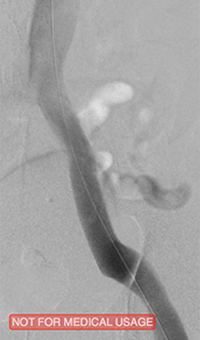

xray of occlusive thrombus extending into the iliac vein.

Occlusive thrombus extending into the iliac vein

xray of femoral vein pre-treatment.

Femoral vein pre-treatment